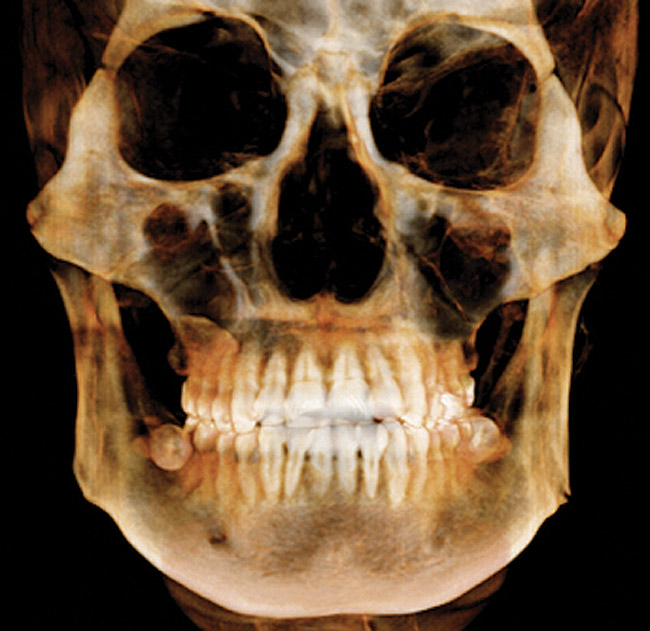

CBCT

CBCT is indicated for the following: implant planning; developing surgical guides; general observation; finding the correct number of canals in abscessed teeth requiring endodontic treatment; in some cases, for orthodontic planning for patients with asymmetries or who need surgical procedures; for evaluation of impacted teeth or TMJ; and as an adjunct for intraoral imaging. Perhaps the most important CBCT advantage is that it offers a “third dimension” for diagnostic accuracy (Figure 3).22

Other benefits include: its short scan time; nearly immediate availability of images; compatibility with practice management software; ability to identify a variety of incidental findings, such as carotid artery calcifications; and facilitate patient communication/education. Like any imaging in dentistry, CBCT should only be used for dental purposes, but incidental findings should be recorded when they are present. CBCT should not be used specifically for screening for carotid calcification, as Duplex Doppler ultrasound is the method of choice for inspecting blood clots in the carotids. When calcification is found in the carotids, or other conditions of general health importance are found, the patient should be referred to the appropriate physician for further follow-up and treatment if needed. While there is a learning curve for reading the full image volumes, there are services available for this. Like CBCT, it is extraoral, so its advantages include that it is more comfortable for patients and can be used in patients who cannot tolerate having a sensor or film in their mouths. It can also be used when intraoral scanning is not practical—eg, for a panoramic bitewing.

It should be emphasized that CBCT should not be considered a replacement for intraoral imaging in the general practice office.19,24 In that regard, pertinent disadvantages are that it offers insufficient detail for diagnosing caries, periodontal disease, and small lesions in the bone. This is due to CBCT beam hardening artifacts and streaking caused by metallic restorations. Additional considerations include its cost, that it requires dedicated operatory space, and that CMS requires facility accreditation and CE for its reimbursement in Medicare or Medicaid patients.25 Also to consider is that it delivers a higher radiation dose than the full-mouth series (FMX) performed with round collimation.24